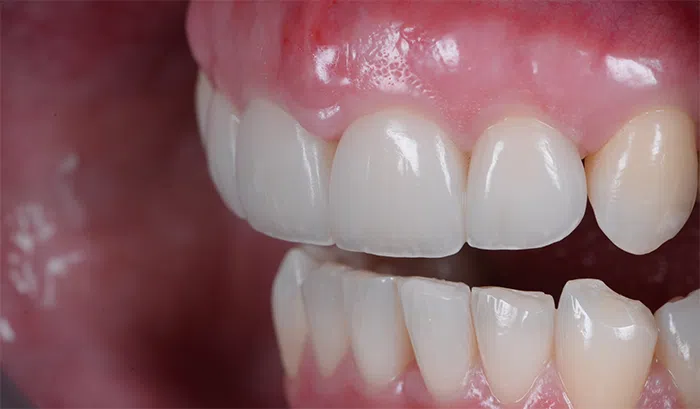

După

Caz de estetică dentară – Fațete ceramică presată E-Max

Provocarea acestui caz a fost în prepararea minim invazivă a dinților centrali rotați și a obține o formă și o culoare cât mai naturală, pacienta dorind un caz de estetică dentară ce să nu fie observabil.

Pacienta a beneficiat de corecție gingivala cu laser pentru uniformizarea asimetriilor gingivale, tratamente endodontice de canal sub microscop, obturațiile vechi (plombe) schimbate cu materiale de compozit cu particule nanoceramice, și fațete dentare din ceramică presată E-Max.

Termen de finalizare 2 săptămâni de la amprentarea finală.